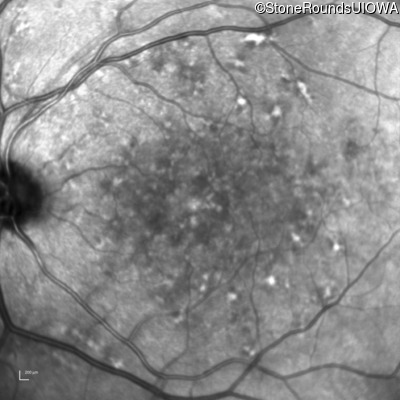

AR Stargardt Disease (IIA)

Age at visit: 59 years (Visit 3)

This 59 year old woman first noticed vision loss in her right eye a few months earlier. She has a cousin with Rhodopsin-associated RP.

Diagnosis & molecular findings

Disease Gene Allele 1 variant(s) Allele 2 variant(s) Inheritance mode

AR Stargardt Disease ABCA4 Arg219Thr AGA>ACA Gly863Ala (G)GA>(G)CA AR